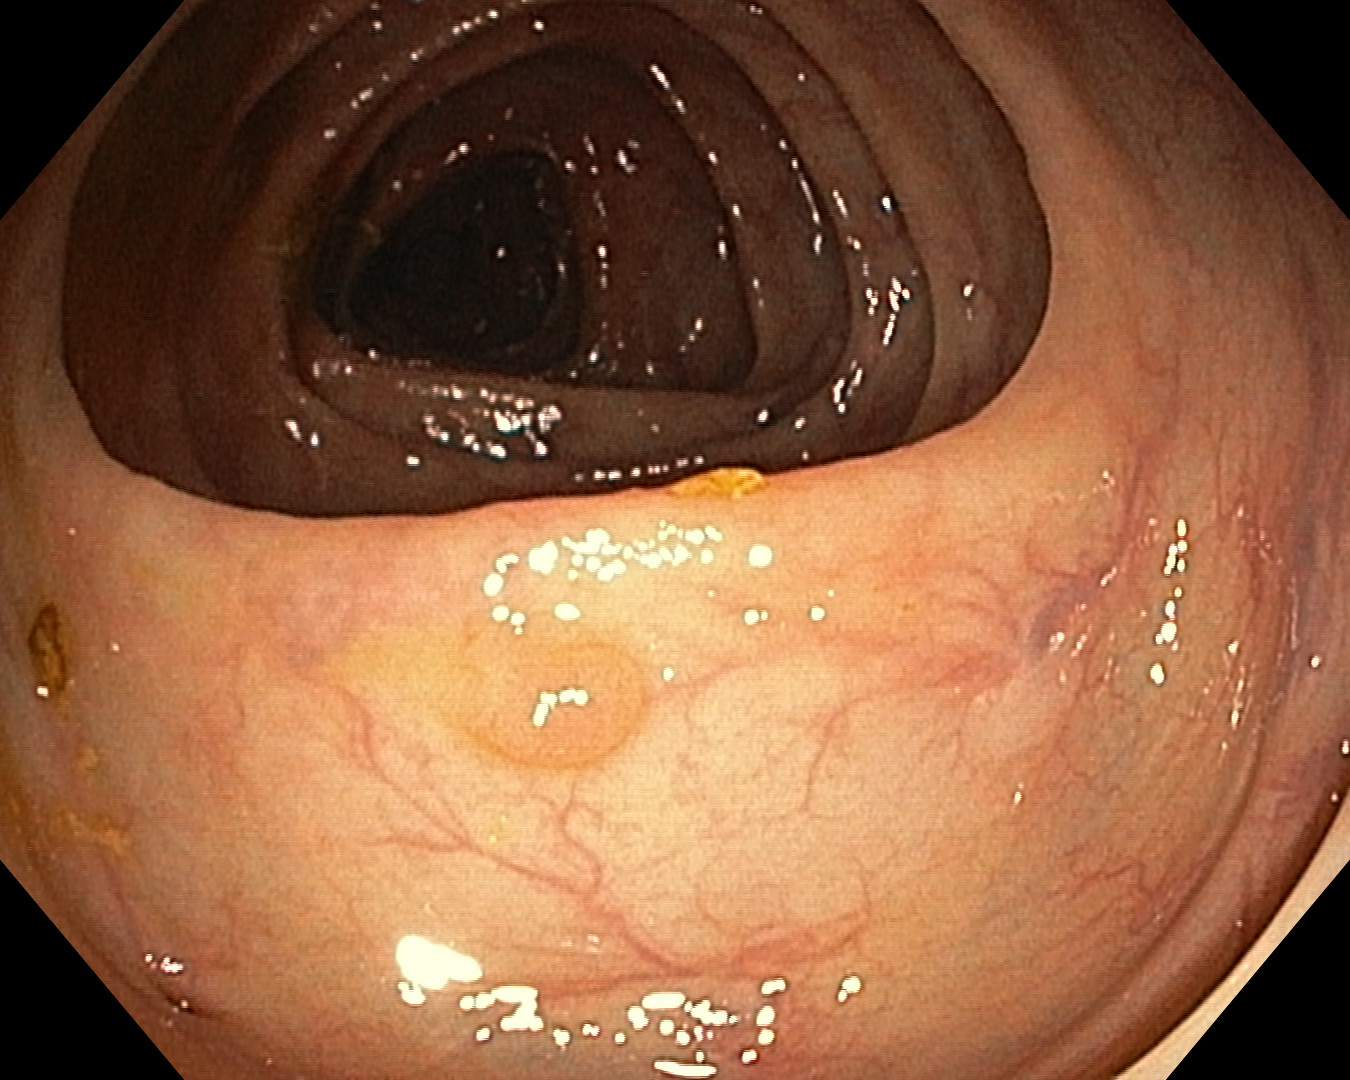

As part of the EndoCV2021 challenge (https://endocv2021.grand-challenge.org/), we were tasked with creating machine learning models that automatically segment polyps [11, 12, 13] in video frames collected from real-world endoscopies. This is a complex task as polyps come in various shapes and sizes, where some (e.g., flat lesions) are barely detectable by even the most experienced endoscopists. Figure 1 shows some of the more difficult examples taken from EndoCV’s development dataset [10] provided by the challenge organizers. The challenge presented two separate tasks, the detection generalization challenge and the segmentation generalization challenge. We participated in the segmentation generalization challenge, where we achieved the best results among 13 other competitors in both rounds. The code for the experiments presented in this paper is available on GitHub111https://github.com/vlbthambawita/divergent-nets.